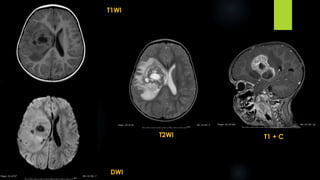

7 year old male with c/o nystagmus and gait abnormality

16 year old male with headache and raised ICT

Pilocytic Astrocytoma (contd.)

 Cystic cerebellar mass with enhancing mural nodule

 Enlarged optic nerve/chiasma/adjacent to 3rd ventricle/brainstem (dotted I sign)

 Less than 10% - solid.

 May enhance in a homogeneous or a heterogeneous fashion

 Approximately 50% are simple cysts with a single mural nodule

 Contrast enhancement is strong

 Calcification (10%)& Hemorrhage are rare

 T1: iso to hypointense solid component compared to adjacent brain

 T2: hyperintense solid component compared to adjacent brain